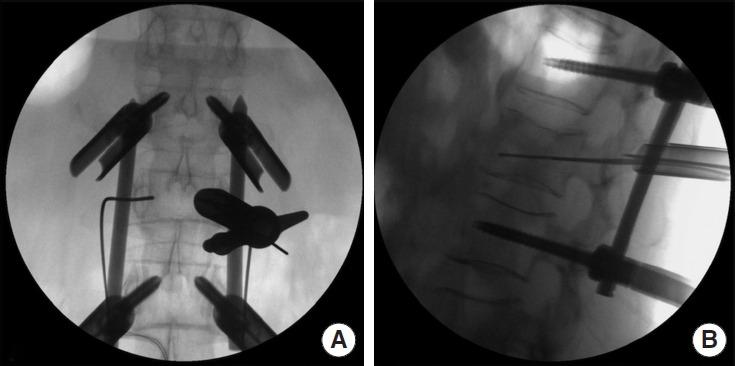

This study aimed to compare the clinical outcomes of patients with AOSpine A3 or A4 thoracolumbar fractures presenting with neurological deficits treated with endoscopic decompression combined with percutaneous pedicle screws fixation (endoscopic minimally invasive surgery, EMIS) or conventional open surgery (OS).

Among the 231 patients who were followed up for more than 2 years, 107 were in the EMIS cohort and 124 were in the OS cohort. Compared with the OS cohort, the EMIS cohort had longer operative time (p<0.05), but the intraoperative blood loss, incision length and hospital stay were significantly reduced (p<0.05). At both postoperative and final follow-up assessments, the EMIS cohort demonstrated significantly better visual analogue scale and Oswestry Disability Index outcomes compared to the OS cohort (p<0.05). Both cohorts maintained similar correction of spinal canal erosion rate, percentage of anterior vertebral height and sagittal Cobb angle after surgery and at the last follow-up (p>0.05). According to American Spinal Injury Association classification, the 2 cohorts had similar neurological recovery at the last follow-up (p>0.05).

In comparison to OS, EMIS treatment for AOSpine A3 or A4 thoracolumbar fractures with neurological deficits has shown comparable clinical efficacy while significantly reducing surgical trauma.